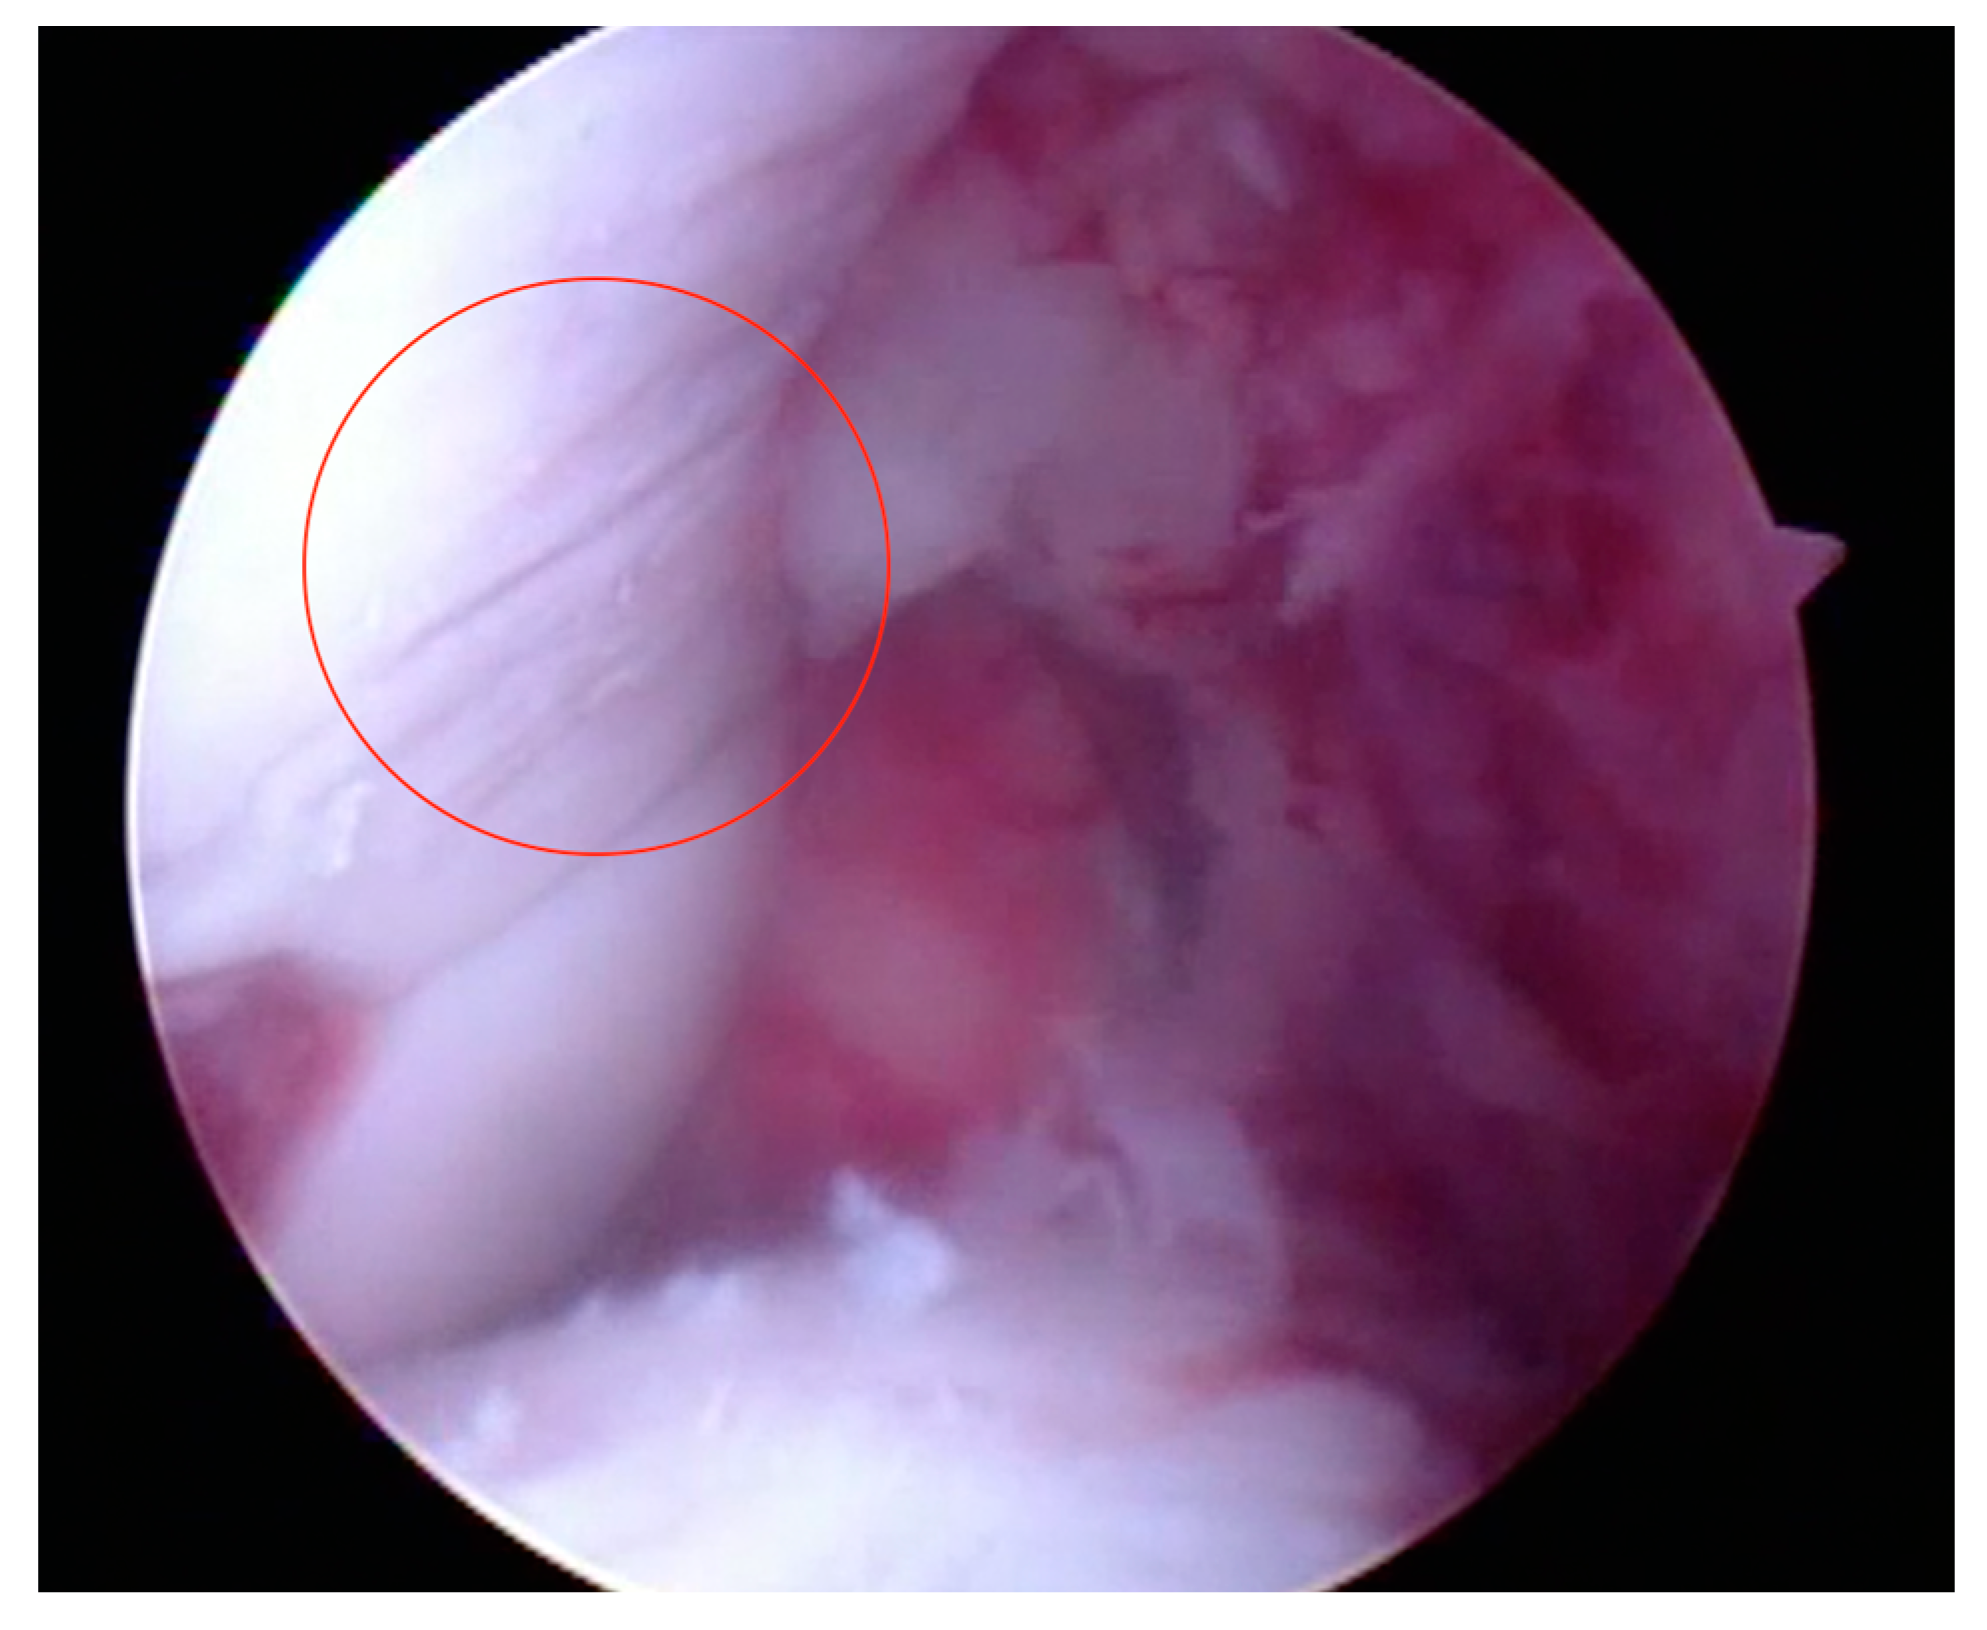

- Articular surface fibrillation (Figure 4)